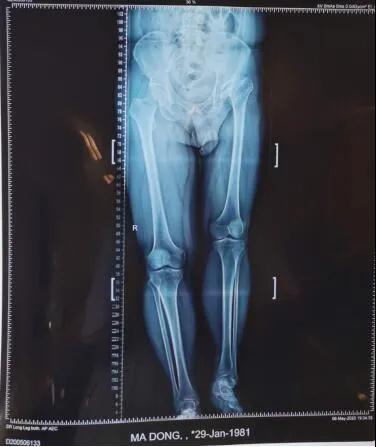

19日,新疆医科大学第六附属医院骨病矫形外科主任李璐兵向记者透露:预计3个月后,有望像正常人一样自如行走。当日,记者在病房走廊看到,马先生手扶助行器,正在练习行走。“17日手术的,今儿就可以下地了。”马先生说。39岁的马先生,年幼时就患有左髋化脓性关节炎,因当时治疗条件有限,造成后期左髋关节骨质破坏严重,左下肢比右下肢短缩了6厘米,走路时跛行很明显,加上左髋关节因为骨质破坏严重导致活动范围受限,就连穿袜子都需要别人帮助。

从拍摄的影像片看出,马先生左侧股骨头已基本消失并且明显上移,错位明显,已与“假”的髋臼形成“假”关节。

术前。

整个手术进行了两个小时,将置换后的髋关节假体准确复位,为患者重建了髋关节并且矫正两条腿基本恢复等长。